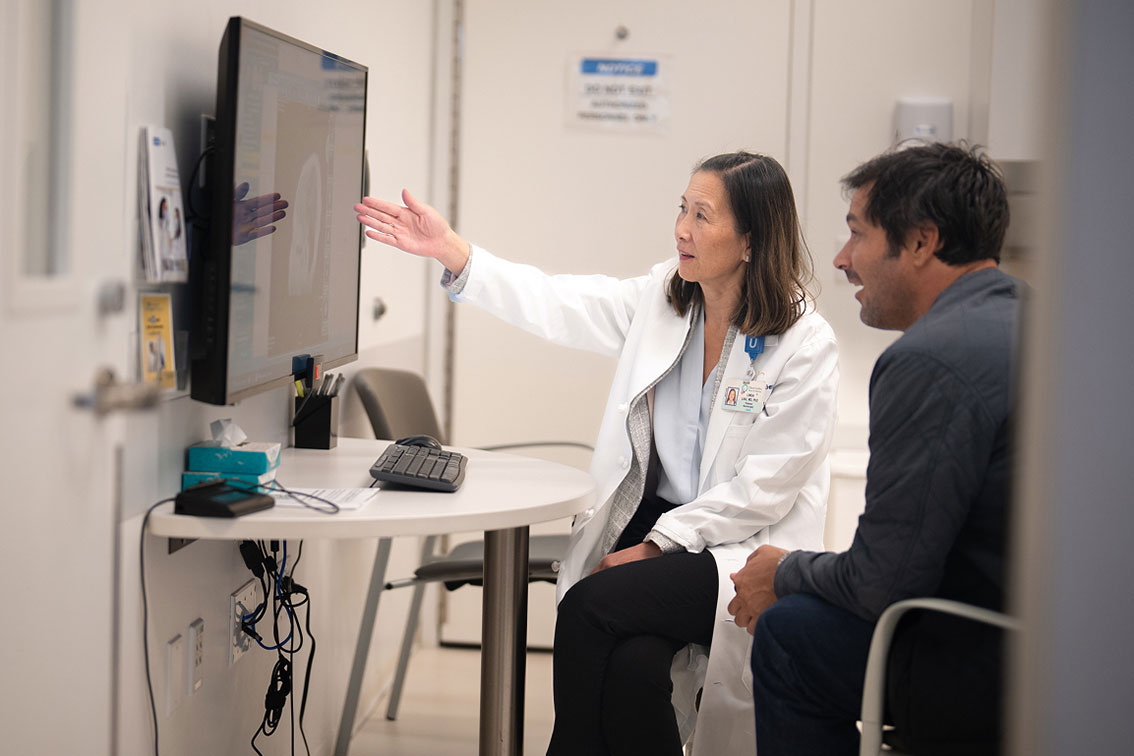

Beating brain cancer through vaccines and research

Across the university, surgeons and scientists are rethinking how to fight brain cancers, particularly glioblastoma, the most aggressive and deadly form of brain cancer. Among them are Linda Liau and Aparna Bhaduri, two researchers at UCLA Health Jonsson Comprehensive Cancer Center leading bold new approaches.